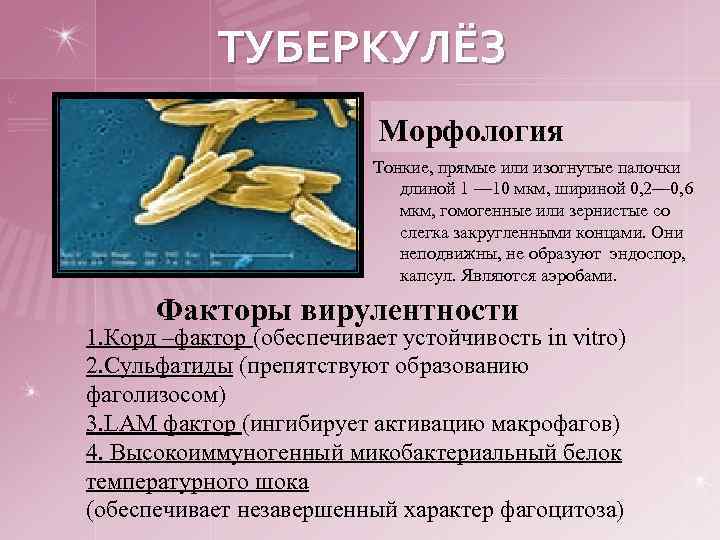

ТУБЕРКУЛЁЗ Морфология Тонкие, прямые или изогнутые палочки длиной 1 — 10 мкм, шириной 0, 2— 0, 6 мкм, гомогенные или зернистые со слегка закругленными концами. Они неподвижны, не образуют эндоспор, капсул. Являются аэробами. Факторы вирулентности 1. Корд –фактор (обеспечивает устойчивость in vitro) 2. Сульфатиды (препятствуют образованию фаголизосом) 3. LAM фактор (ингибирует активацию макрофагов) 4. Высокоиммуногенный микобактериальный белок температурного шока (обеспечивает незавершенный характер фагоцитоза)